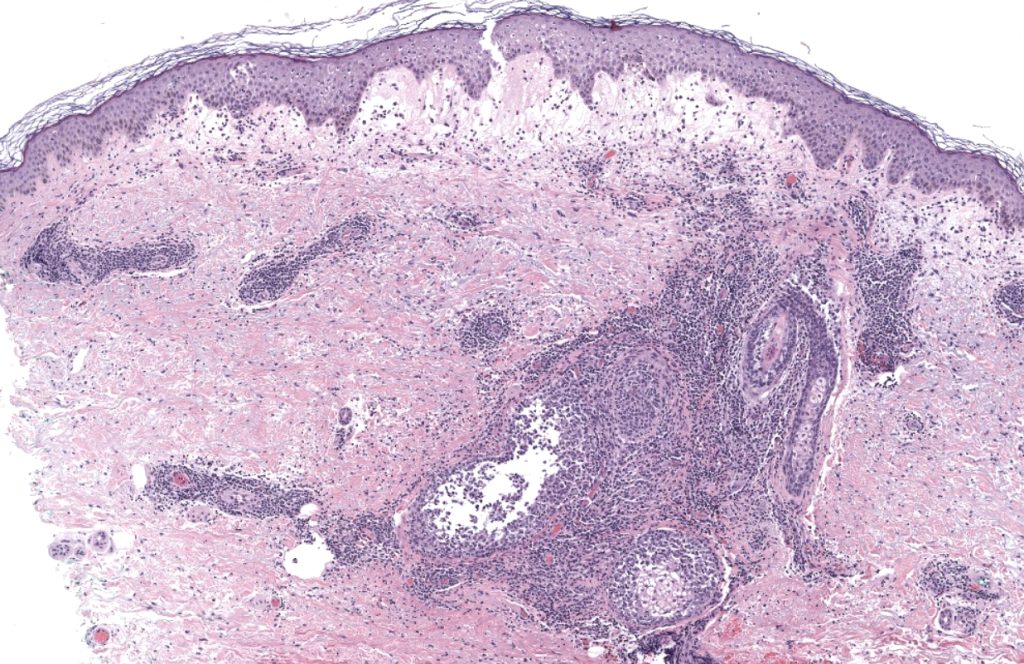

- Definición: dermatosis inflamatoria caracterizada por inicio abrupto de pápulas/nódulos/placas eritemato-violáceas dolorosas, acompañadas con frecuencia de fiebre y marcadores inflamatorios elevados, con infiltrado dérmico neutrofílico (típicamente sin vasculitis primaria). Sweet 1964, Cohen 2007

- Confirmación: biopsia punch. Guhl 2008